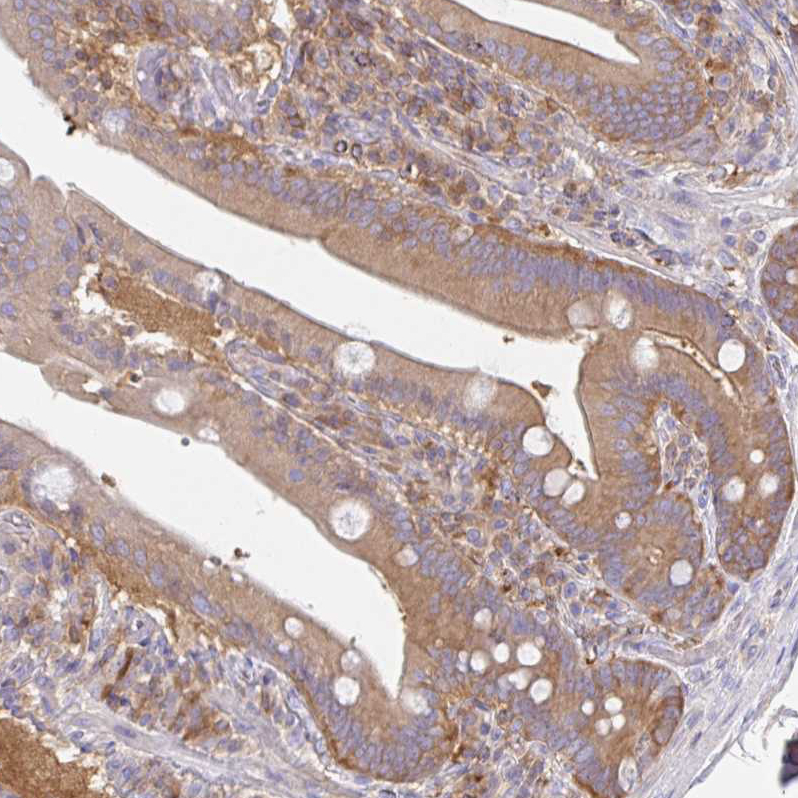

Immunohistochemical staining of human cerebellum shows strong cytoplasmic positivity in Purkinje cells.